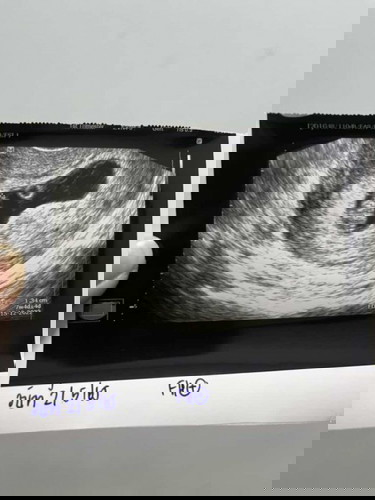

แม่ๆเจอน้องตอนอายุครรภ์กี่สัปดาห์บ้างค่ะ บ้านนี้เจอ 7w4D เจอตัวน้องพร้อมหัวใจน้อง💕 ท้องแรกค่ะ❤️

ช่วงนี้มีปวดท้องน้อยนิดๆด้วยค่ะ ไม่รู้อัตรายหรือเปล่า ใครมีประสบการณ์แชร์ได้เลยนะคะ